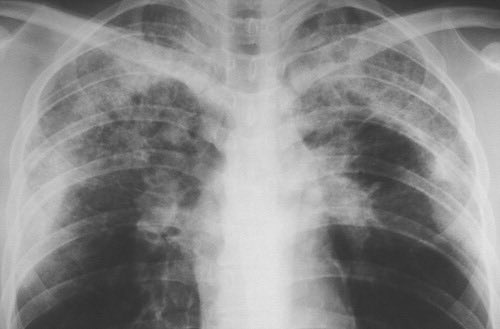

المستوى: صعب جدا Pulmonary edema بس القلب ابدا ماله شغل ! اللي يعرف وش نسميها ويعرف التشخيص اللي يجي معها بنرقيه رزدنت R4